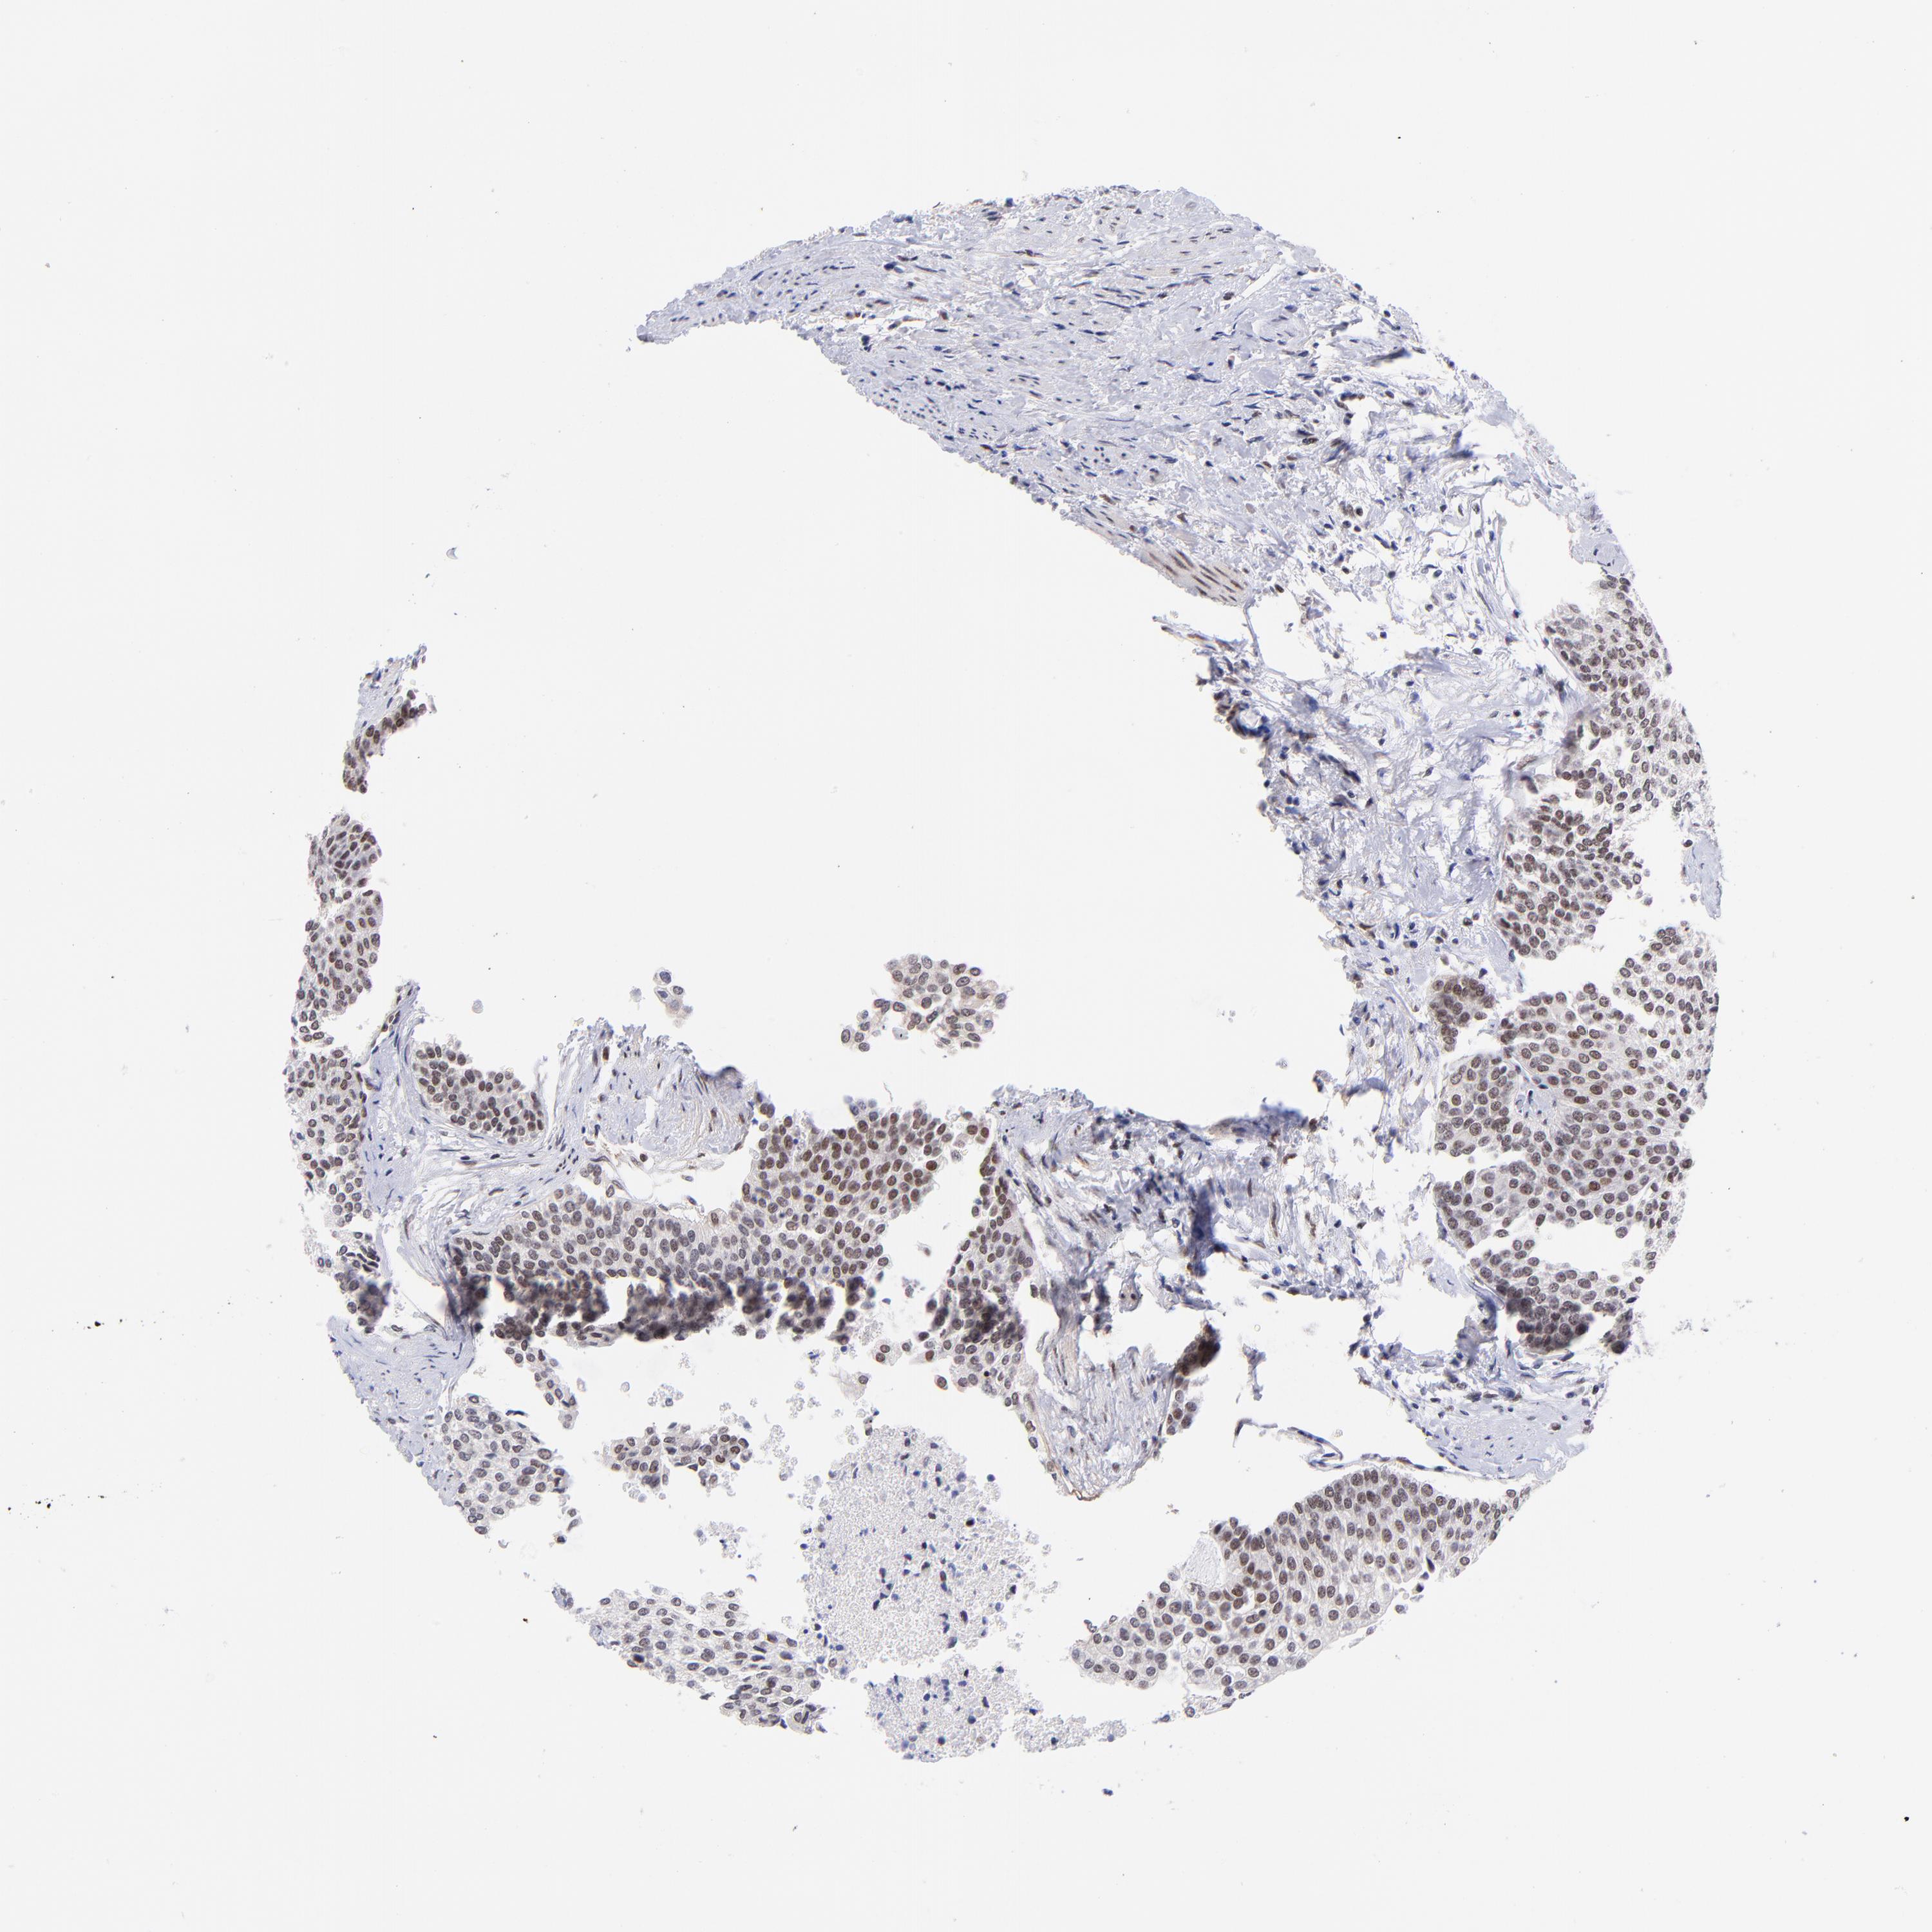

UROTHELIAL CANCER - Protein expressioni

A mouse-over function shows sample information and annotation data. Click on an image to view it in a full screen mode. Samples can be filtered based on level of antibody staining by selecting one or several of the following categories: high, medium, low and not detected. The assay and annotation is described here.

Note that samples used for immunohistochemistry by the Human Protein Atlas do not correspond to samples in the TCGA dataset.

Antibody stainingi

Antibody staining in the annotated cell types in the current human tissue is reported as not detected, low, medium, or high, based on conventional immunohistochemistry profiling in selected tissues. This score is based on the combination of the staining intensity and fraction of stained cells.

Each image is clickable and will lead to virtual microscopy that enables deeper exploration of all samples and also displays staining intensity scores, fraction scores and subcellular localization as well as patient and tissue information for each sample.

Antibody HPA003111

Staining

High

Medium

Low

Not detected

Intensity

Strong

Moderate

Weak

Negative

Quantity

>75%

75%-25%

<25%

None

Location

Nuclear

Cytoplasmic/membranous

Cytoplasmic/membranous,nuclear

Urothelial carcinoma, High grade

Urothelial carcinoma, Low grade